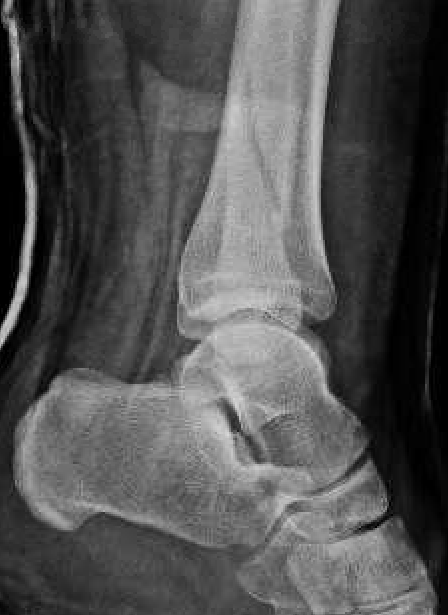

![]() |

Weber A fibular fracture

Definition

Fracture below level of syndesmosis

Fibular avulsion fracture

Management

Stable

Full weight bear

Weber B fibular fracture

Fracture at level of syndesmosis

Supination-external rotation Type IV

Syndesmosis stable - management depends on deltoid ligament